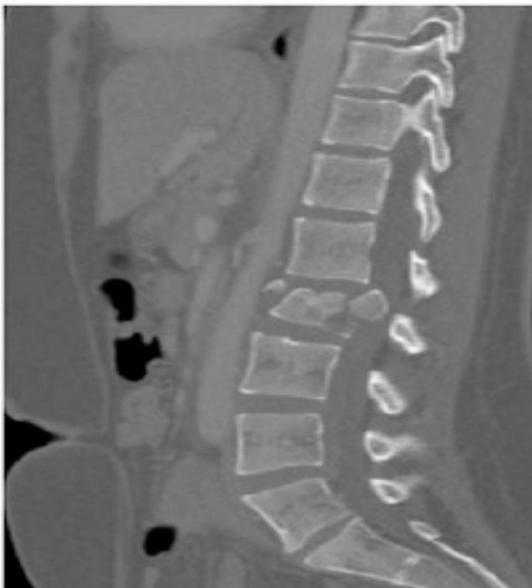

This patient has back pain radiating down to his right leg. examine the back

| Item | Procedure | Technique … | Attachments |

| On Patient | Standing, tilting forwards with hand on left side of lower back | ![]() | |

| Local (Back, Shoulder, Flanks, Chest) | Position (best in standing), Views (Posterior, Lateral, Anterior), Normal curves and alignment | ![]() | |

| Major Deformity and Swelling Assessment | Shoulder height, Deformity, Flanks, Space between arm and trunk, Masses | ![]() | |

| Extra Items | Support (braces, walkers, etc.), Dressings | ![]() | |

| Anatomic Local Examination | |||

| Systematic Assessment | Skin (swelling, scars, color, hair, dryness), Subcutaneous (lymph nodes, veins, nerves, tendons), Muscles (bulk, wasting, twitches), Bones (landmarks, swelling, angulation, deformity), Joints (position, swelling, redness) | ![]() | |

| Proper Exposure | ![]() | ||

| Comprehensive Look Assessment | ![]() | ||

| Feel | Tenderness Assessment | Generalized (to start with), Specific (Spinous processes, Sacroiliac joints, Paravertebral muscles) | ![]() |

| Temperature Assessment | Compare distal/proximal, Compare right/left | ||

| Anatomic Assessment | Skin (dryness, scars), Subcutaneous (nodules), Muscles (Paravertebral: spasm, bulk, tenderness), Bones (landmarks: spinous processes, iliac crest, coccyx - tenderness, mass), Joints (sacroiliac tenderness) | ||

| Move | General Motion Assessment | Change of shape/deformity during motion, Smoothness of motion, Extent (Range) | ![]() |

| Specific Movements | |||

| Flexion and Extension | ![]() | ||

| R and L lateral flexion | Sideway Bending | ![]() | |

| R and L rotation | Must be in Sitting position, help patient understand rotation movements | ![]() | |